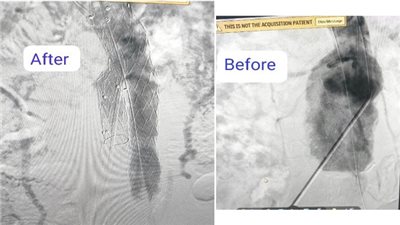

جامعة القاهرة تحقق إنجازًا طبيًا وتنقذ مريضًا بعملية نادرة لتغيير الصمام الأورطي

نجاح جديد لمستشفى بدر الجامعى فى إجراء تركيب قسطرة دقيقة بواسطة فريق جراحة الأوعية الدموية